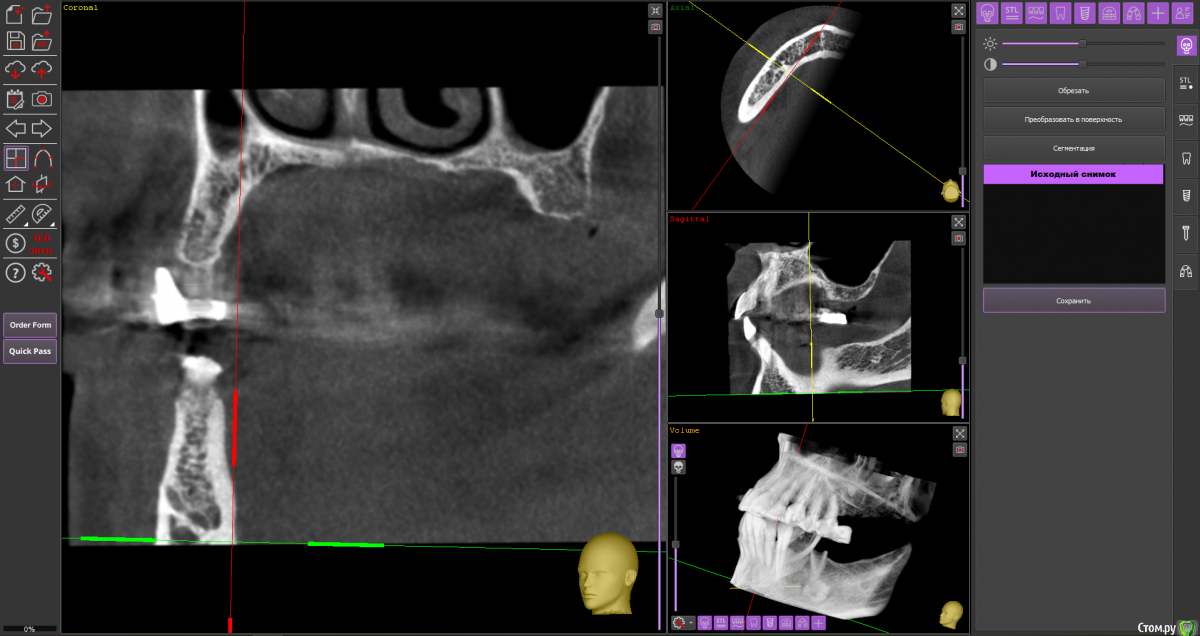

Fin Опубликовано 6 мая, 2020 Поделиться Опубликовано 6 мая, 2020 Здравствуйте коллеги. Пришла пациентка, для установки импланта в обл 3.6. После осмотра КТ обнаружил образование в проекции будущего импланта. В ходе осмотра КТ так же обнаружилось несколько подобных образований по НЧ. Помогите советом, кто сталкивался с подобной ситуацией и что это может быть? Ссылка на комментарий

Дмитрий Л. Опубликовано 6 мая, 2020 Поделиться Опубликовано 6 мая, 2020 Ну сделайте трепан биопсию. Через пару недель можно будет и имплант вкрутить. Я думаю что это костный рисунок. Ссылка на комментарий

wladdX Опубликовано 6 мая, 2020 Поделиться Опубликовано 6 мая, 2020 (изменено) Мне тоже кажется, что вы принимаете балочную структуру и петли н\ч канала за н\образование. Такое встречается иногда. Похожий случай На ОПТГ выглядит уже не так трагично Изменено 6 мая, 2020 пользователем wladdX 1 Ссылка на комментарий

It'sGeorgy Опубликовано 6 мая, 2020 Поделиться Опубликовано 6 мая, 2020 Тоже часто сталкиваюсь с таким. Костный рисунок. 1 Ссылка на комментарий

Fin Опубликовано 7 мая, 2020 Автор Поделиться Опубликовано 7 мая, 2020 Мне тоже кажется, что вы принимаете балочную структуру и петли н\ч канала за н\образование. Такое встречается иногда. Похожий случай46_1.jpg На ОПТГ выглядит уже не так трагичноОПТГ фрагмент.jpgЧестно говоря тоже думаю, что костный рисунок но смутили размеры и то что в других местах кроме этих таких явлений не наблюдается. Сейчас пациент предоставил снимок до ортод. лечения. На нем немного видно костный рисунок. Ссылка на комментарий

Fin Опубликовано 7 мая, 2020 Автор Поделиться Опубликовано 7 мая, 2020 Тоже часто сталкиваюсь с таким. Костный рисунок.Извините, хотел нажать кнопку ответа а поставил минус((.Такое тоже вижу очень часто, но смущают размеры. Ссылка на комментарий